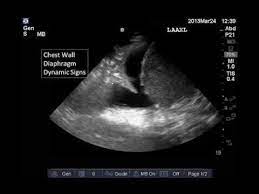

Loculated Pleural Effusion On Ultrasound - Ultrasound In The Diagnosis And Management Of Pleural Effusions Abstract Europe Pmc - On the patient's right side the diaphragm, the liver, and the vertebral line can be seen.. A parasternal long axis and subcostal views are shown. Most pleural effusions, whether free flowing or loculated, are hypoechoic with a sharp echogenic line that delineates the visceral pleura and lung. Both the trocar and the modified seldinger techniques can be used. In no case was pneumothorax produced. Ultrasound of a loculated pleural effusion.

On the patient's right side the diaphragm, the liver, and the vertebral line can be seen. Approximately 1.5 million patients are diagnosed with pleural effusion each year in the united states. Conventional chest radiography and computed tomography (ct) scanning are the primary imaging modalities that are used for evaluation of all types of pleural disease, but ultrasound and magnetic resonance. A transudate is always anechoic in nature, while an exudate may show the following features: Other causes are complicated parapneumonic effusion , empyema, and tuberculosis. The trocar technique is faster and easier. Six patients with either malignant pleural effusion or empyema, in whom multiple conventional attempts at thoracocentesis were unsuccessful, were evaluated by ultrasound. Images were examined for the presence of pleural effusion and fibrin strands within the effusion.

Ct (in a) and ultrasound (in b) revealing loculated pleural effusion. Chest ct and chest ultrasound images were also examined for parenchymal consolidation and the presence of lung necrosis or abscess. A parasternal long axis and subcostal views are shown. Note that the pigtail catheter in a is positioned below (rather than within) the loculated effusion, which explains why the catheter did drain any fluid until it was subsequently. Six patients with either malignant pleural effusion or empyema, in whom multiple conventional attempts at thoracocentesis were unsuccessful, were evaluated by ultrasound. 1 pleural effusion is defined as abnormal fluid collection in the pleural space. Note the presence of a fibrin strands extending from the lung to the diaphragm, resulting in loculations of the pleural effusion. Ultrasound can aid in the diagnosis of pleural effusion. A hemothorax on pulmonary ultrasound typically appears an effusion with a homogenous echogenic appearance 2 . The trocar technique is faster and easier. This is the shred or fractal sign. E7.8 loculated effusion loculated effusion. Both the trocar and the modified seldinger techniques can be used.

Pleural effusion is assessed by ultrasound placing the transducer in the midaxillary line with the marker oriented toward the patient's head. Thoracocentesis of loculated pleural effusions using grey scale ultrasonic guidance. Note the presence of a fibrin strands extending from the lung to the diaphragm, resulting in loculations of the pleural effusion. Level a) for the detection of effusion, lung ultrasound is more accurate than supine radiography and is as accurate as ct. The first anechoic effusion surrounds collapsed lung which contains small aerated patches.